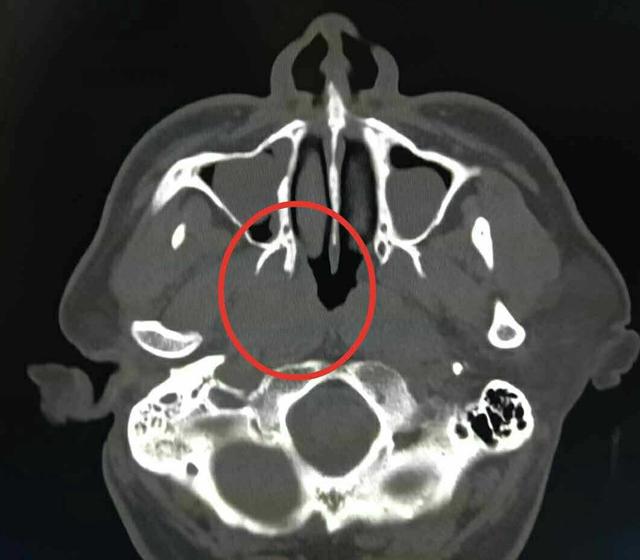

鼻咽癌

图片尺寸1238x1080